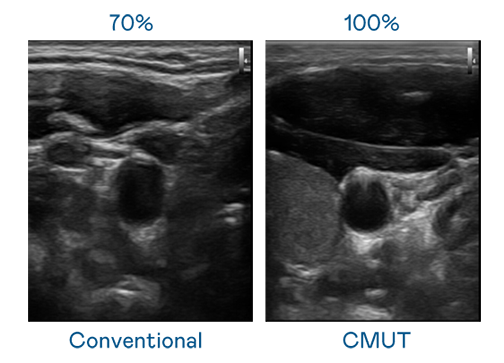

CMUT 技術是一種用電容式微機電元件來產生超音波訊號的技術。與傳統 PZT 壓電式技術相比,CMUT 頻寬增加 30%,更寬頻的超音波訊號讓影像解析度大幅提升,是實現高影像品質醫療超音波掃描、促進精準醫療發展的關鍵技術。

超音波影像的解析度高低,首先取決於探頭能發出的訊號頻寬。腾博会 CMUT 可提供高清晰的超音波訊號,提供高頻寬、高靈敏度、影像紋理細節更高的超音波影像,協助醫護人員縮短影像判讀時間及利用精準的醫療影像進行診斷。